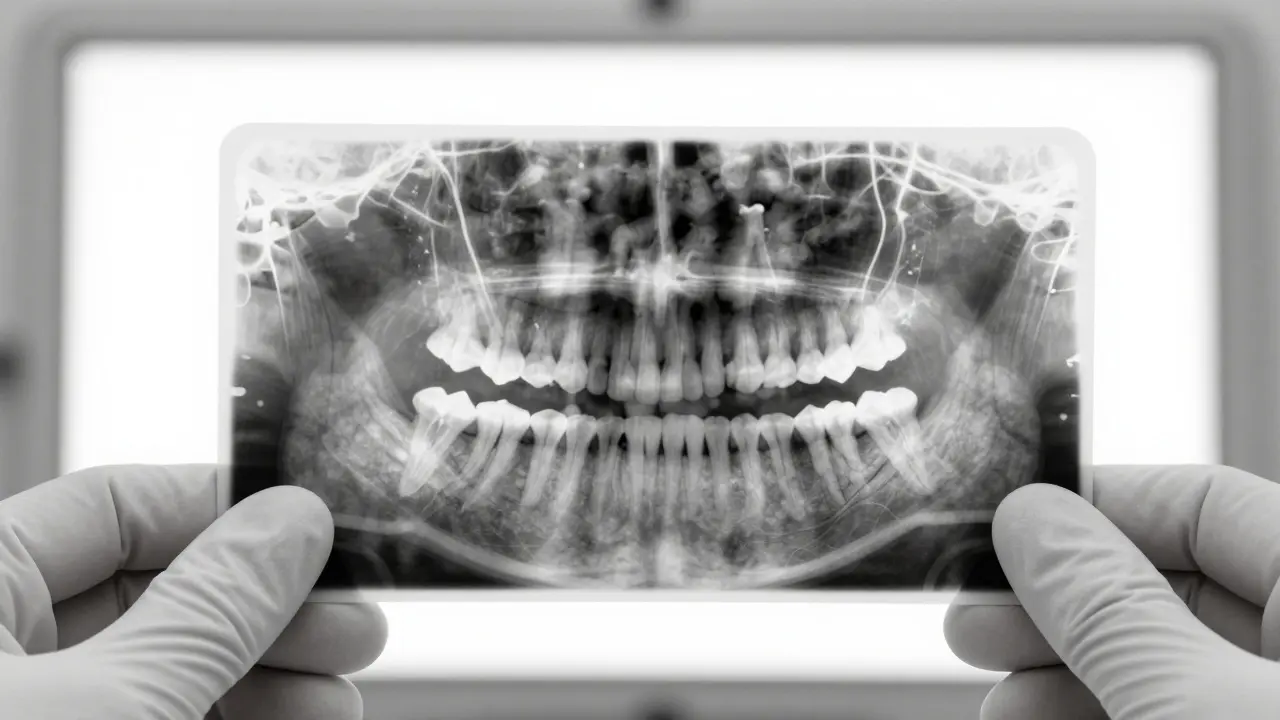

Dentální rentgen osmiček a sedmiček

Před odstraněním osmiček provede stomatolog dentální rentgen. Tento snímek ukáže přesnou polohu zubů a jejich vztah k okolním strukturám. Podle výsledků se rozhodne o nejlepším postupu.